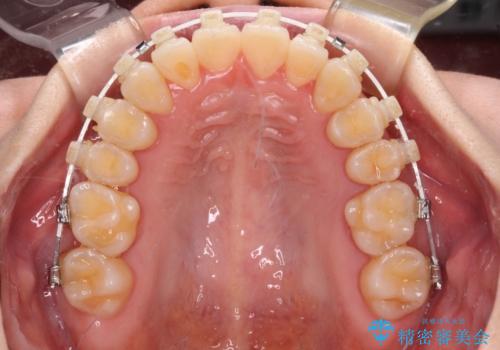

- 審美装置

- 治療計画

- 下顎前歯の欠損により隙間ができていることを気にして来院された患者様です。

下顎前歯が2歯欠損しており、スペースになっており、上顎は叢生歯列となってしました。

周囲の歯を削らないようにするためインプラントがおすすめとなりますが、歯根の移動が不十分な場合にはインプラントを埋入する幅が獲得できないため、その場合にはオールセラミックブリッジにより補綴治療を行うこととして、矯正治療を行うこととしました。

当初は上記計画でしたが、レントゲン撮影よりインプラント埋入は困難と判断され、患者様と相談の上、歯を削ってブリッジとするよりも、奥歯の咬み合わせを多少妥協することとなっても、スペースを閉じて仕上げていくこととしました。